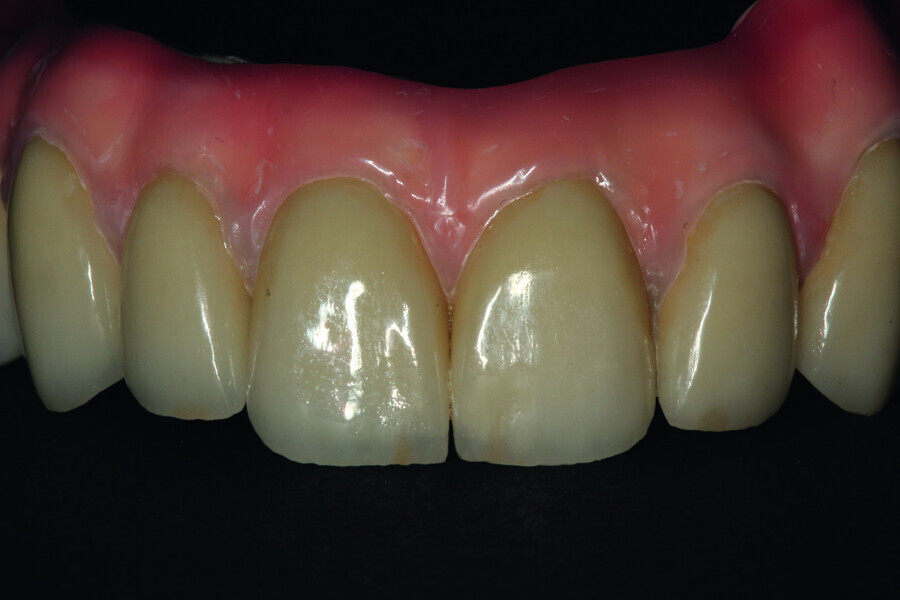

Fig. 24: Final restoration—frontal view.

Fig. 25: Magnification showing precision in the making of the crowns and in veneering by means of pink composite.